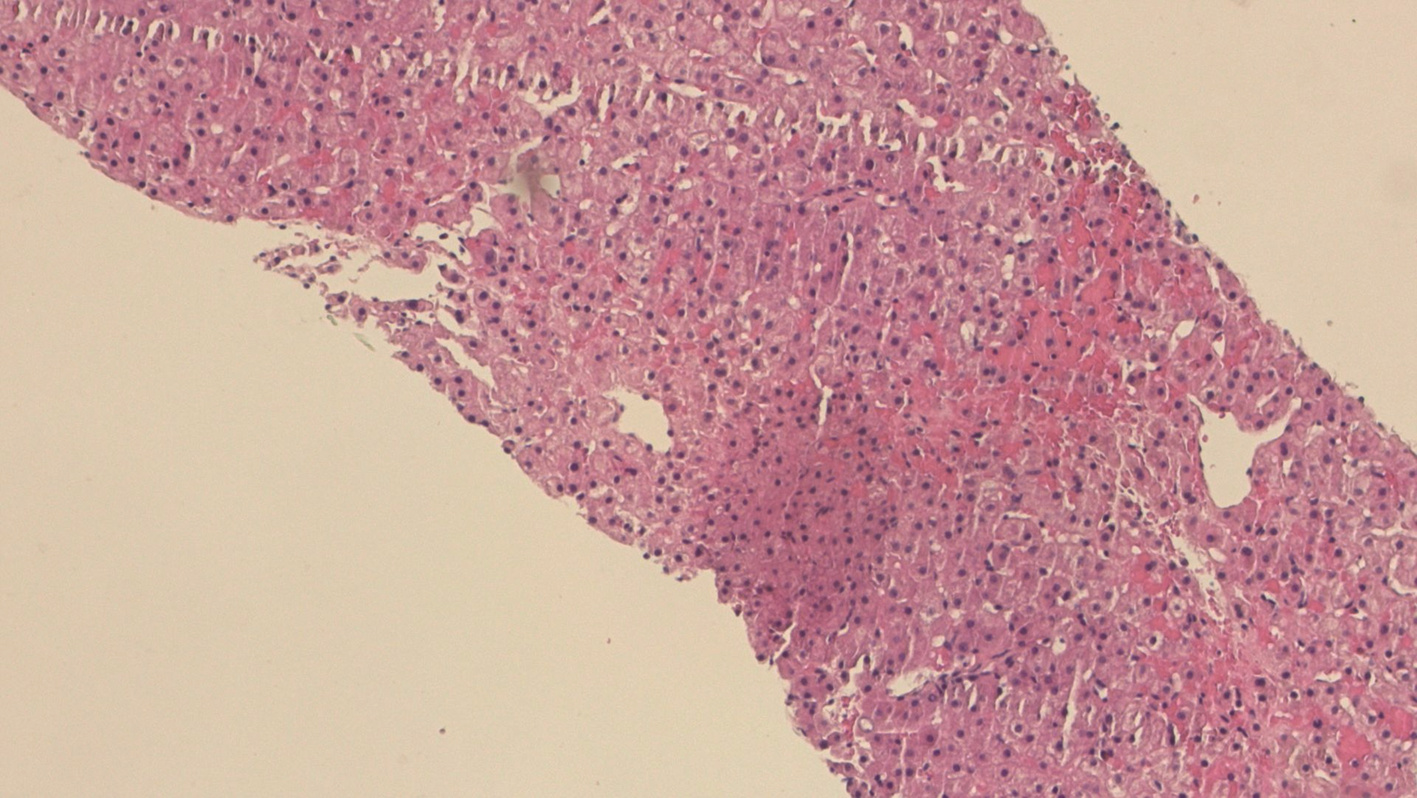

基于超声造影LI-RADS特征的肝细胞癌微血管侵犯列线图模型的构建及验证

2022, 38(11): 2520-2525. DOI: 10.3969/j.issn.1001-5256.2022.11.016

摘要(882) HTML (345) PDF (2938KB)(63)

摘要:

目的  基于肝细胞癌(HCC)患者的超声造影(CEUS)肝脏成像报告和数据系统(LI-RADS)特征建立预测微血管侵犯(MVI)的列线图模型并进行验证。  方法  选取2017年1月—2020年7月在江苏大学附属武进医院确诊的HCC患者共262例,按照1∶ 1比例随机分为建模组和验证组各131例,以术后镜下病理结果确诊MVI,其中建模组MVI 70例和验证组MVI 56例。采用超声造影评估两组的LI-RADS特征。两组间计量资料比较采用独立样本t检验;两组间计数资料比较采用χ2检验。采用单因素和多因素Logistic回归分析筛选建模组MVI的危险因素;绘制受试者工作特征曲线(ROC曲线),计算模型预测MVI的曲线下面积(AUC),评估预测准确度;应用决策曲线分析模型的一致性,比较模型预测MVI的校正曲线与标准曲线的离散度。  结果  建模组与验证组患者的临床资料和CEUS检查结果比较,差异均无统计学意义(P值均>0.05)。单因素分析显示,与MVI阴性患者相比,MVI阳性患者血清AFP水平显升高,肿瘤直径增大,LI-RADS显示LR-5“后出”和LR-M“先出”增多,LI-RADS分级较高,差异均有统计学意义(P值均<0.05)。多因素分析显示,AFP 20~400 ng/mL(OR=2.65,P<0.001)、AFP≥400 ng/mL(OR=3.98,P<0.001)、肿瘤直径≥30 mm(OR=2.12,P<0.001)和CEUS显示LR-M(OR=3.24,P<0.001) 是MVI的独立危险因素。ROC曲线显示,列线图预测建模组和验证组MVI的AUC分别为0.867和0.821。列线图模型的一致性指数C-Index为0.765(95%CI:0.701~0.834)。在建模组和验证组,列线图模型的预测校准曲线与标准曲线均接近。  结论  利用CEUS得出LI-RADS,并结合AFP和肿瘤直径建立的列线图模型有较好的应用价值,有助于指导临床术前筛选MVI高危患者,制订恰当的手术方案。